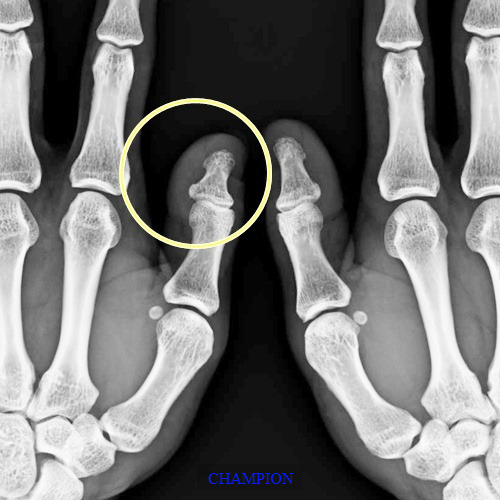

엄지 단지증은 엄지손가락의 첫마디 뼈가 굵고 짧아서 생기는 구조적 특징으로, 이 때문에 손가락과 손톱이 정상 방향으로 자라지 못하고 개구리 손 형태로 발달합니다.

단지증 네일은 단지증으로 인해 손가락과 손끝 구조가 평평하거나 굵고 짧아지며 넓적하게 생긴 손가락과 손톱 변형을 말합니다.

엄지 단지증과 함께 나타날 때 단지증 네일이 두드러지며, 개구리 손톱이나 우렁손톱 형태로 변형을 유발합니다.

- 손가락과 조갑이 뼈 모양대로 짧고 넓적함

- 조갑판이 정상 각도로 자라지 못함

- 뼈 모양의 구조적인 문제